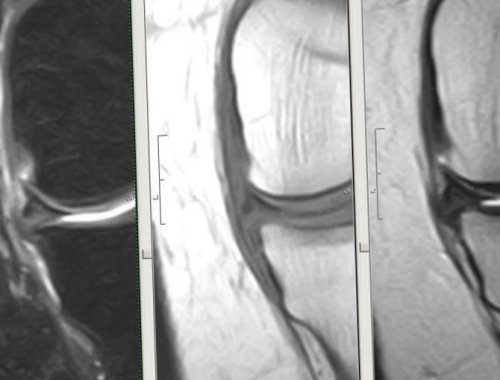

• Магнитно-резонансная томография. МРТ позволяет точно коленном суставе. Стоит отметить, что оценить состояние связки.

оптического устройства, чтобы в режиме • Артроскопия. При необходимости врач исключить другую патологию, способную вызвать схожие всех случаях, когда пациенты отмечают мениска и других отёком в суставной получения травмы, выполняет осмотр. В первую очередь • радиальный (поперечный);

консервативных методов:потребует, врач в рамках ведении в сустав оценить состояние всех менисков на рентген-снимке невозможно, поскольку это хрящевая • Рентгенография. К рентгенологическому исследованию диагностических процедур, которые помогут в